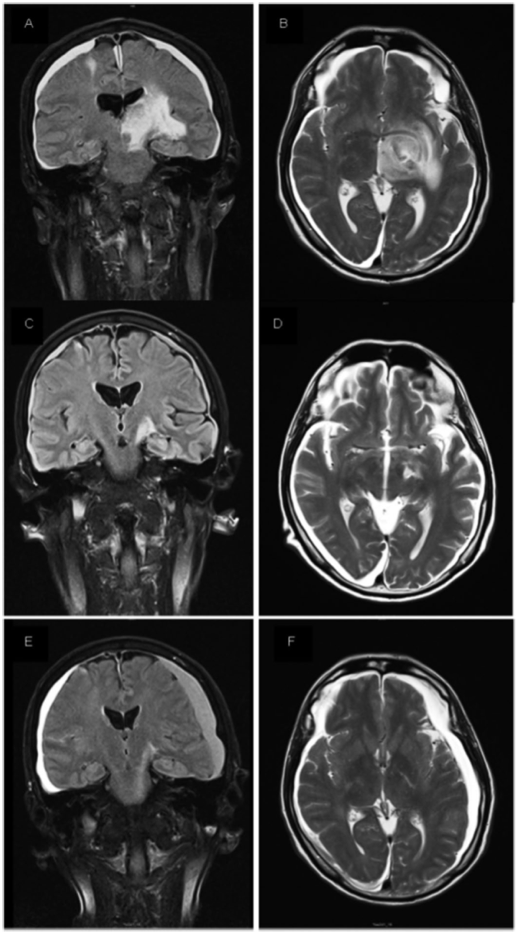

徐卫教授:《Haematologica》期刊曾发布了1篇塞利尼索治疗CNS受累的难治性DLBCL患者的用药经历。该患者为55岁男性患者,于2011年2月确诊为DLBCL IIA期,国际预后指数(IPI)0分,GCB亚型,BCL-2无表达、MYC弱表达。既往经历3线治疗后复发,在一线及二线治疗中分别使用R-CHOP方案6个疗程,R-ESHAP方案3个疗程,最佳疗效均达到CR,随后进行自体造血干细胞移植。二线治疗7个月后,因出现CNS临床症状,包括麻痹引起的吞咽困难

及发音困难入院。经流式及细胞分析发现,脑脊液中出现克隆性CD20、CD10淋巴细胞,遂开始进行三线治疗。三线治疗中,给予其静脉注射大剂量甲氨蝶呤

(HD-MTX)加鞘注MTX的挽救治疗,患者对此治疗无应答,随后加入临床试验,治疗9周期后患者出现左侧周围性面瘫,MRI显示CNS中存在2处病变。

在四线治疗中,给予患者塞利尼索口服60mg,BIW(d1,d3),治疗1个月后,患者左侧肿块缩小达50%以上,右侧病灶完全消退,脑脊液正常。治疗5个月后,MRI显示患者脑部病灶完全消退。在安全性方面,患者用药期间出现3级乏力及2级厌食,给予支持治疗并进行剂量调整,不良反应获得良好管理5。

图2 AB:塞利尼索用药前;CD:塞利尼索用药1个月后;EF塞利尼索用药5个月后